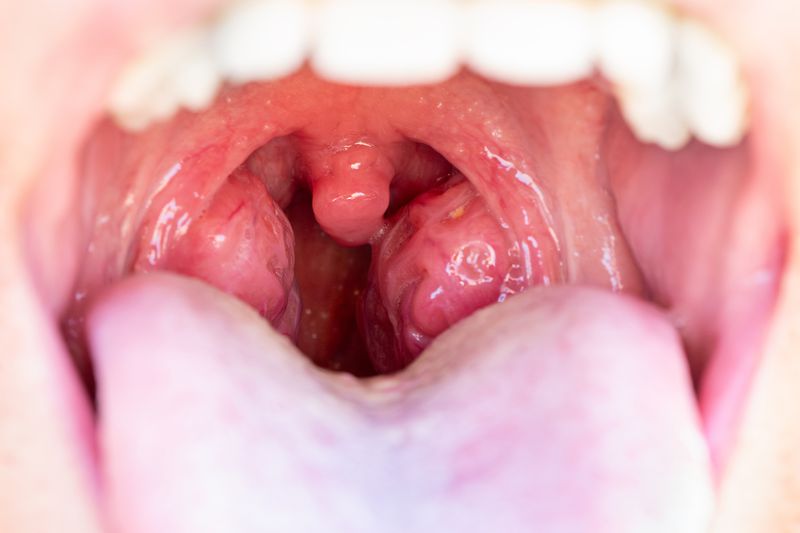

Фарингит — заболевание, которому характерно воспаление слизистой оболочки глотки. Он развивается вследствие влияния агрессивного фактора, например, различного рода инфекций и химических веществ. Чаще всего острый фарингит появляется в осеннее и весеннее время, это связано с распространением вирусов в этот период. Заболевание имеет ярко выраженные симптомы и требует незамедлительного обращения к врачу. Пациенту важно начать терапию до распространения инфекции на нижние дыхательные пути. Запущенная стадия заболевания является одной из причин воспаления легких.

В начале общее состояние пациента при развитии недуга сильно не изменяется. Больной ощущает небольшой дискомфорт в горле, ему кажется, что в глотке находится инородное тело. Со временем появляются болевые ощущения во время приема пищи и питья. С каждым днем они все более усиливаются. Если инфекция распространилась на область слуховых труб, то у пациента начинает закладывать уши. Спустя время появляется сухой кашель, а затем гнойная мокрота. Если недуг возник на фоне развития скарлатины, кори или респираторной вирусной инфекции, то к признакам добавляется клиника основной патологии. Симптомы фарингита у взрослого без температуры следующие:

Острой форме заболевания характерно увеличение лимфоузлов. Оно сопровождается болезненностью во время пальпации. У пациента в особо сложных случаях сильно повышается температура, он ощущает общую слабость.

Острый фарингит у взрослых — воспаление задней стенки глотки, сопровождающееся болью и першением. Игнорирование состояния может вызвать переход в хроническую форму и повторные эпизоды. Считаю необходимым соблюдение гигиены и отказ от раздражающих факторов. Диагностика проводится фарингоскопией и анализом жалоб. Лечение включает антисептики, полоскания и, при бактериальной форме — антибиотики. Без терапии возможна дисфункция голоса и дискомфорт.